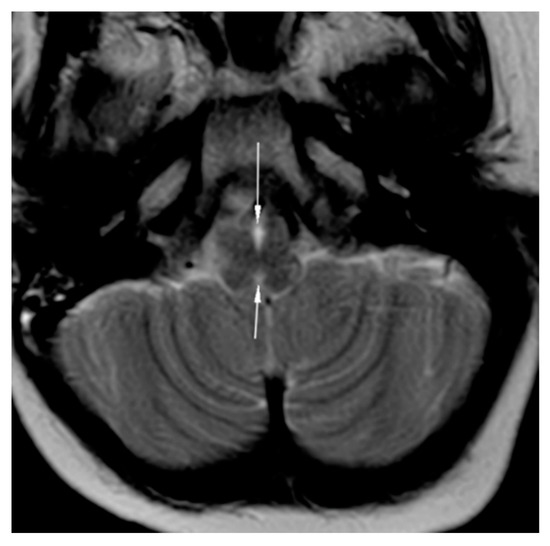

Brain magnetic resonance imaging (MRI) demonstrated hypoplasia of the brainstem (Figure 2), a left thalamus volume larger than the right (Figure 3), an enlarged fourth ventricle, an anterior and posterior midline bulbar and pontine cleft (split-pons sign) (Figure 4), a butterfly configuration of the medulla (Figure 5), an occipital and parietal plagiocephaly on the right side, and a slight benign enlargement of the subarachnoid spaces in the frontotemporal area. There were no signal changes within the medulla or pons in any of the brain MRI sequences.

Figure 5. MRI brain axial T2-weighted image showing butterfly medulla oblongata.